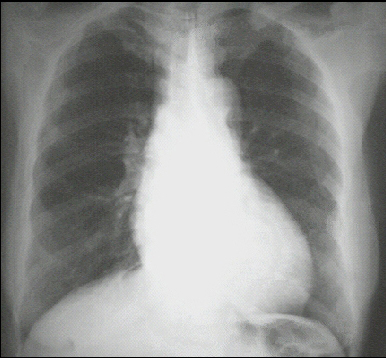

These chest X rays show left ventricular enlargement and a dilated aorta The PA view demonstrates cardiomegaly, as evidenced by a cardiothoracic ratio greater than 50%. Note also the increased inferolateral cardiac border that is consistent with ventricular enlargement due to volume overload. The ascending, transverse, and descending aortic shadows are also prominent.